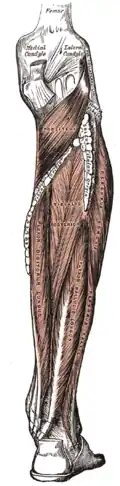

Right knee-joint, from the front, showing interior ligaments. Muscles of the back of the leg. Deep layer.

Muscles of the back of the leg. Deep layer.- Right knee in extension. Deep dissection. Posterior view.